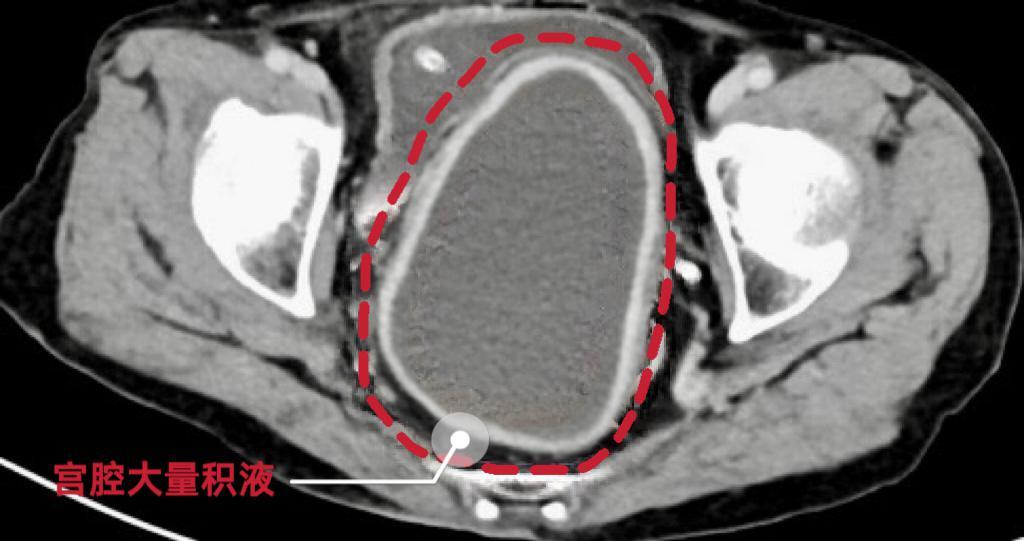

绝经女性警惕!八旬老太腹痛入院,医生从她宫腔抽出约250ml腥臭味黄绿色脓液 88岁的王奶奶(化名)近日因宫腔积脓合并严重低血糖、感染性休克入院,经过长沙市中心医院(南华大学附属长沙中心医院)妇产科一区、内分泌科、超声科、营养科等多学科团队联合救治,老人病情稳定,康复出院。 该院妇产科一区黄佼主任介绍,经过询问家属病史了解到,老人一个月前出现过腹痛情况,后面伴随有精神食欲差、嗜睡、逐渐消瘦等症状。此次入院时老人神志模糊,血压下降,血糖波动剧烈,最低血糖仅1.7mmol/L,生命体征极不稳定,腹部CT显示盆腔内巨大包块,考虑“宫腔积脓、感染性休克、严重低血糖”立即收治入院。 面对复杂病情,黄佼主任团队积极给予抗感染、抗休克及严密监测各项指标,迅速联合内分泌科、超声科、营养科等多学科专家进行会诊。内分泌科团队首先针对患者严重低血糖问题展开紧急处理,通过调整补糖速度、持续血糖监测等措施,使患者血糖逐渐趋于稳定。营养科则为患者制定了个性化的静脉营养支持方案,提供能量支持。 在血糖控制稳定后,黄佼主任团队为患者实施了彩超引导下的阴道内镜下宫颈管粘连分离及脓液引流术,术中发现患者阴道萎缩环状缩窄明显、宫颈管严重粘连,内镜下分离粘连后发现宫腔内积聚大量黄绿色、带有腥臭味的脓液。经过精心操作,成功引流出脓液约250ml。术后患者神志逐渐清醒,血压回升,血糖稳定,感染指标明显下降。 术后,医护团队为患者制定了详细的康复计划,包括抗感染治疗、血糖监控、营养支持及心理疏导等。在全体医护人员的精心照料下,患者病情迅速好转,各项指标恢复至正常范围,最终康复出院。 “宫腔积脓又称子宫积脓,指宫腔内炎性分泌物引流不畅,积聚于子宫腔内形成的感染性疾病,是盆腔炎性疾病的特殊表现形式。宫腔积脓的平均发病率约为0.1%—0.3%,绝经后女性的发病率则高达13.6%。”黄佼主任提醒,女性绝经后卵巢功能衰退,雌激素分泌减少,导致阴道壁及子宫内膜萎缩变薄,自净能力降低,病原体易上行感染宫腔。同时,子宫颈及宫颈管萎缩变硬,宫颈外口狭窄甚至呈针尖状,宫腔积液不易排出,继发感染形成宫腔积脓。 典型的宫腔积脓“三联征”表现为阴道流脓排液、绝经后阴道流血和下腹痛,但早期患者一般无明显症状。仅有10%的患者出现典型的三联征,半数患者无明显临床表现,因此宫腔积脓的早期临床诊断较为困难。若治疗不及时,可能引发严重并发症,甚至危及生命。特别是高龄患者,由于症状不典型,免疫力下降,更易发生感染扩散。因此,老年人一旦出现下腹疼痛、发热、异常分泌物等症状,应及时就医,以免延误病情。 来源:潇湘晨报